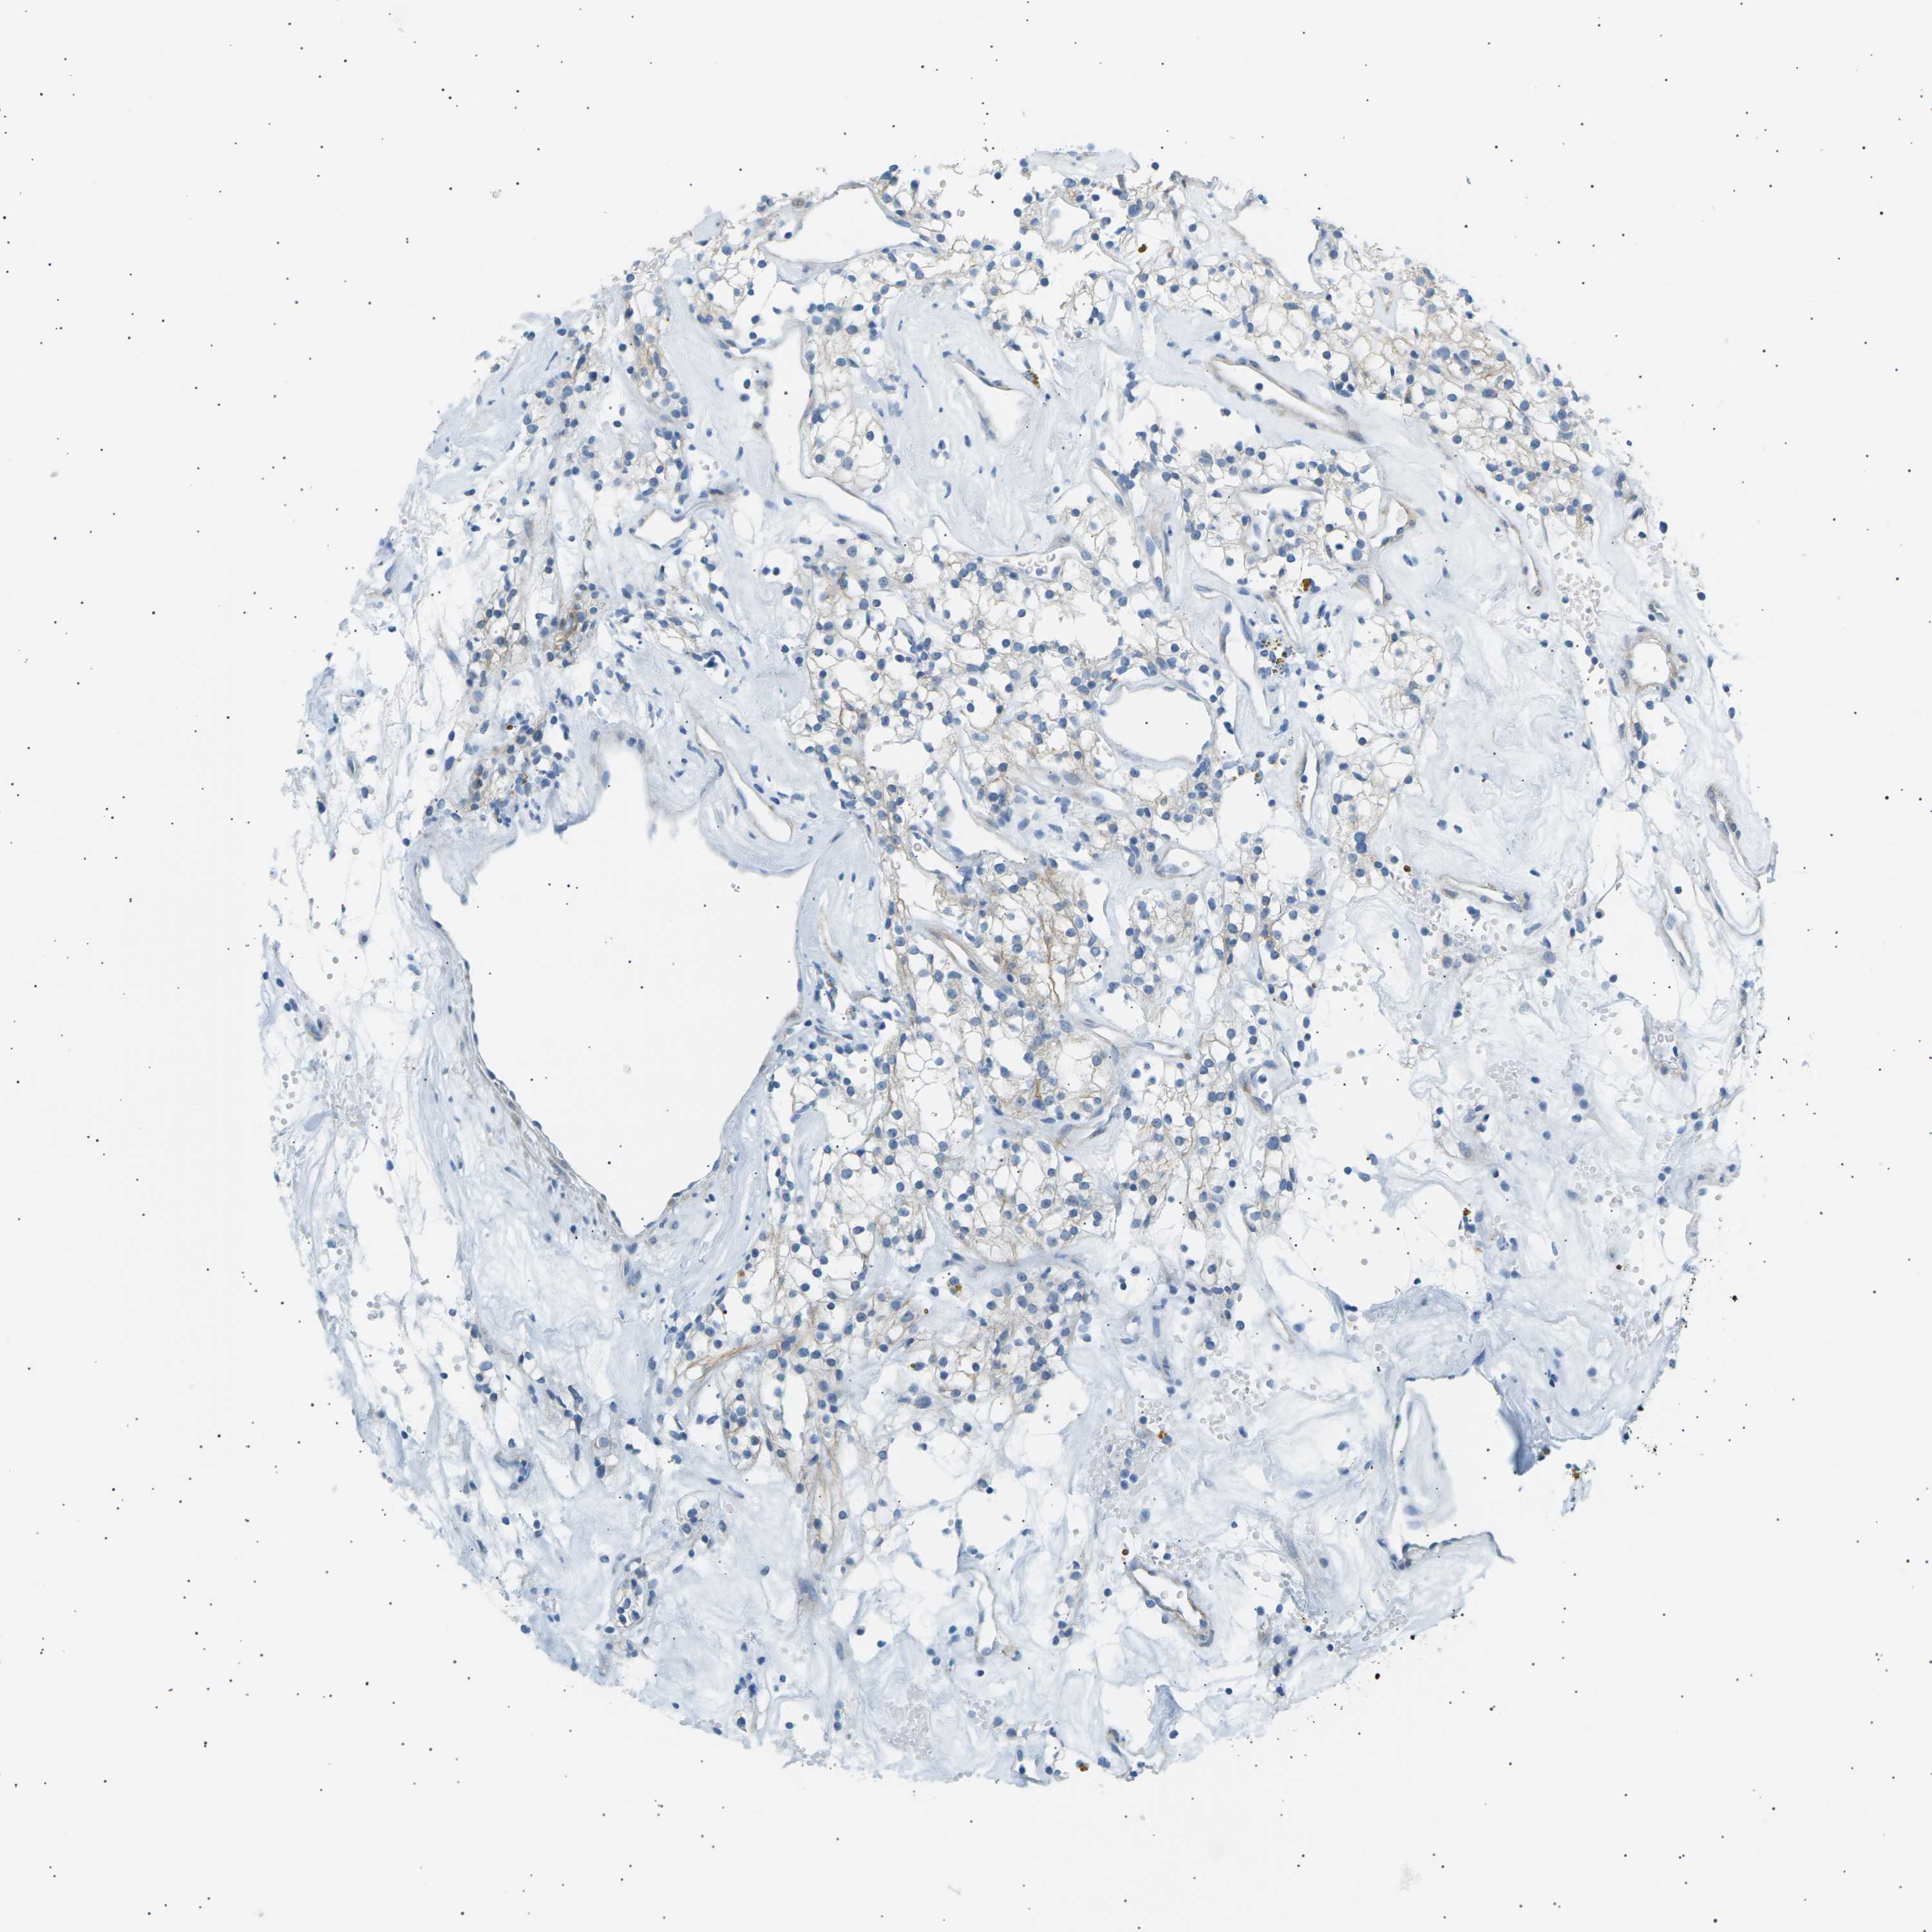

KIDNEY RENAL CLEAR CELL CARCINOMA (VALIDATION) - Interactive survival scatter ploti

The Survival Scatter plot shows the clinical status (i.e. dead or alive) for all individuals in the patient cohort, based on the same data that underlies the corresponding Kaplan-Meier plots. Patients that are alive at last time for follow-up are shown in blue and patients who have died during the study are shown in red.

The x-axis shows the expression levels (FPKM) of the investigated gene in the tumor tissue at the time of diagnosis. The y-axis shows the follow-up time after diagnosis (years). Both axes are complimented with kernel density curves demonstrating the data density over the axes. The top density plot shows the expression levels (FPKM) distribution among dead (red) and alive patients (blue). The right density plot shows the data density of the survived years of dead patients with high and low expression levels respectively, stratified using the cutoff indicated by the vertical dashed line through the Survival Scatter plot. This cutoff is automatically defined based on the FPKM cutoff that minimizes the p-score. The cutoff can be changed by dragging the vertical line or by entering a cutoff value in the square labeled "Current cut-off".

Under the Survival Scatter plot the p-score landscape (black curve; left axis) is shown together with dead median separation (red curve; right axis). Dead median separation is the difference in median mRNA expression between patients who have died with high and low expression, respectively. It is calculated as follows: median FPKM expression of dead patients with high expression - median FPKM expression of dead patients with low expression. This is intended to aid the user in visually exploring custom cutoffs and the associated p-scores and dead median separation.

Individual patient data is displayed and can be filtered by clicking on one or more of the category buttons on the top of the page. Categories describing expression level and patient information include: high, low, alive, dead, female, male and tumor stages. The scale of the x-axis can be toggled between linear and log-scale by clicking on the "x log" button. Mouse-over function shows TCGA ID, patient information and mRNA expression (FPKM) for each patient.

& Survival analysisi

Kaplan-Meier plots summarize results from analysis of correlation between mRNA expression level and patient survival. Patients were divided based on level of expression into one of the two groups "low" (under cut off) or "high" (over cut off). X-axis shows time for survival (years) and y-axis shows the probability of survival, where 1.0 corresponds to 100 percent.

SEPTIN5 is not prognostic in Kidney Renal Clear Cell Carcinoma (validation)

Best expression cut offi

Based on the FPKM value of each gene, patients were classified into two groups and association between prognosis (survival) and gene expression (FPKM) was examined. The best expression cut-off refers the FPKM value that yields maximal difference with regard to survival between the two groups at the lowest log-rank P-value. Best expression cut-off was selected based on survival analysis .

When clicking on this number, the vertical dashed line indicating cut-off, the interactive survival plot, and the Kaplan-Meier curve will be adjusted to show results based on the best expression cut-off.

: 7.92

P scorei

Log-rank P value for Kaplan-Meier plot showing results from analysis of correlation between mRNA expression level and patient survival.

N/A

TCGA RNA samplesi

RNA-seq data is reported as average FPKM (number Fragments Per Kilobase of exon per Million reads), generated by the The Cancer Genome Atlas (TCGA) .

Normal distribution across the dataset is visualized with box plots, shown as median and 25th and 75th percentiles. Points are displayed as outliers if they are above or below 1.5 times the interquartile range. FPKM values of the individual samples are presented next to the box plot.

Average pTPM 15.3

Number of samples 100